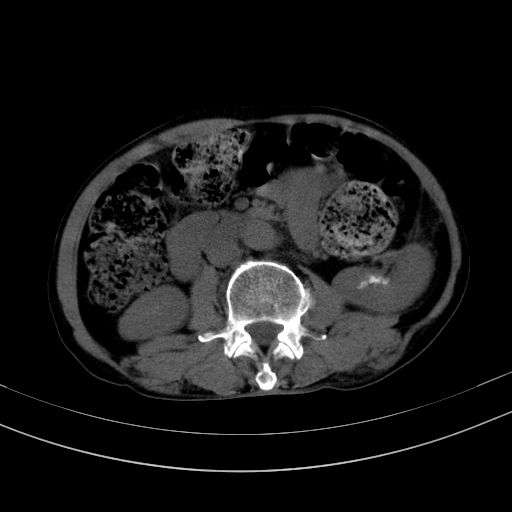

以下是引用37度在2010-1-9 14:37:00的发言:[br]1.双肾囊肿,左肾积水结石,.胆总管轻度扩张;[br]2.病灶在腹膜外,考虑纤维瘤。

以下是引用dyqct在2010-1-9 17:56:00的发言:[br]考虑:1.双肾囊肿,左肾积水结石、旋转不良。[br] 2.右侧腹直肌血肿或纤维瘤。[br]肠道准备不好。做个增强。